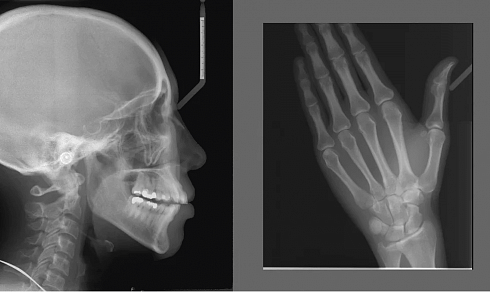

- Основные панорамные и цефалометрические программы (в комплекте): Стандартная панорама взрослого, Стандартная панорама ребенка, — Боковой двойной ВНЧС, Двойной задне-передний ВНЧС, Задне-передний синус (прямой слой), Боковая и передне-задняя цефалометрические проекции, Проекция кисти.